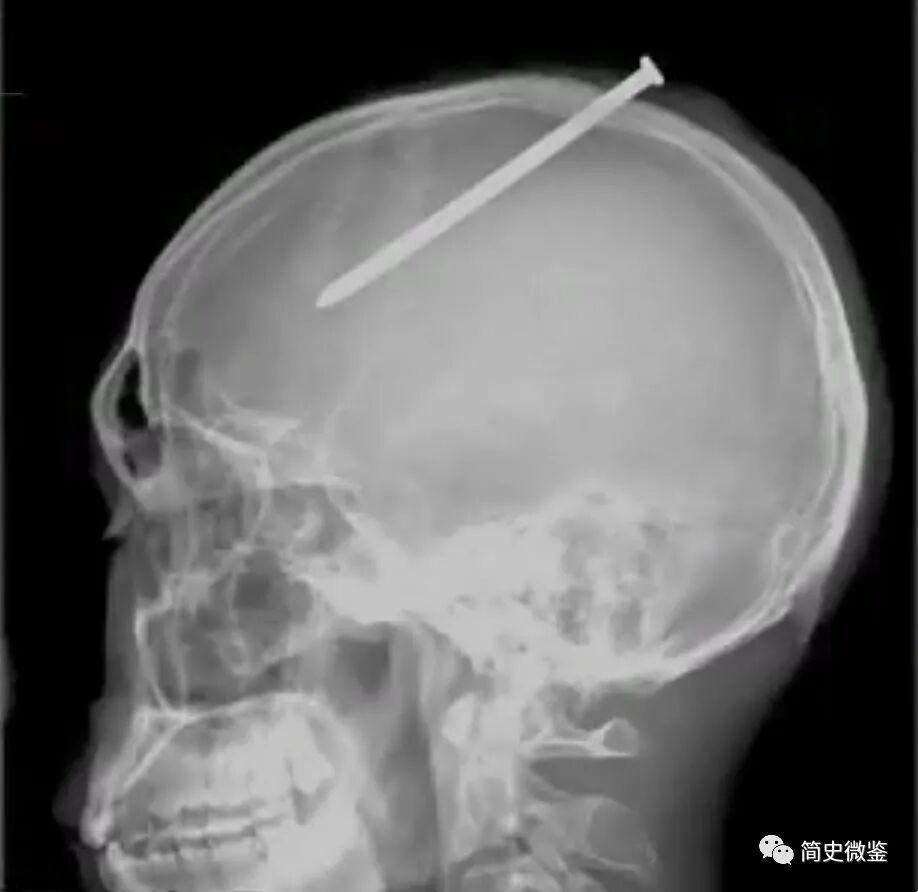

CT结果很快就出来了,上面显示钉子长10厘米左右,从小陈的左侧头顶部,从后往前斜扎进去,经过了中央前回后斜向前,来到了左侧额叶的位置。

医生告诉小陈,这颗钉子所进入的区域,刚好是控制语言中枢和运动中枢的地方,所以小陈才会出现四肢不听使唤,语言功能障碍的情况。

而小陈已经出现了右侧肢体偏瘫的征兆,也和左侧顶叶、颞叶受伤有关。

同时,医生推测,小陈之所以能像个没事儿人一样走动,是因为钉子进入的位置很巧妙,恰巧避开了一些比较重要的血管,其中有一个叫做矢状窦的地方特别危险,颅内大部分血液循环中的静脉回流都是通过矢状窦来完成的。

做个比喻的话,矢状窦就像是一个装满了血的小血包,而且它不像动脉静脉那样可以有肌肉收缩,有凝血止血的功能,一旦被钉子碰到,就可能造成大出血,出现生命危险!

幸运的是,这颗钉子虽然几乎和矢状窦贴在了一起,但还有一点点距离,刚好没有伤到矢状窦,这才逃过一劫。

小心地打开小陈的头颅后,医生发现钉子的位置比想象中还要危险,距离矢状窦仅有1厘米左右的距离,只要稍微偏上一点,小陈就完了!

一厘米、两厘米……终于,一颗十厘米左右的钢钉被完整地取了出来,落在一旁的手术盘里,发出一声脆响。

手术十分成功,这颗在小陈脑袋里待了35天的钉子终于被取了出来,当哥哥看到这颗钉子时,长舒了一口气。